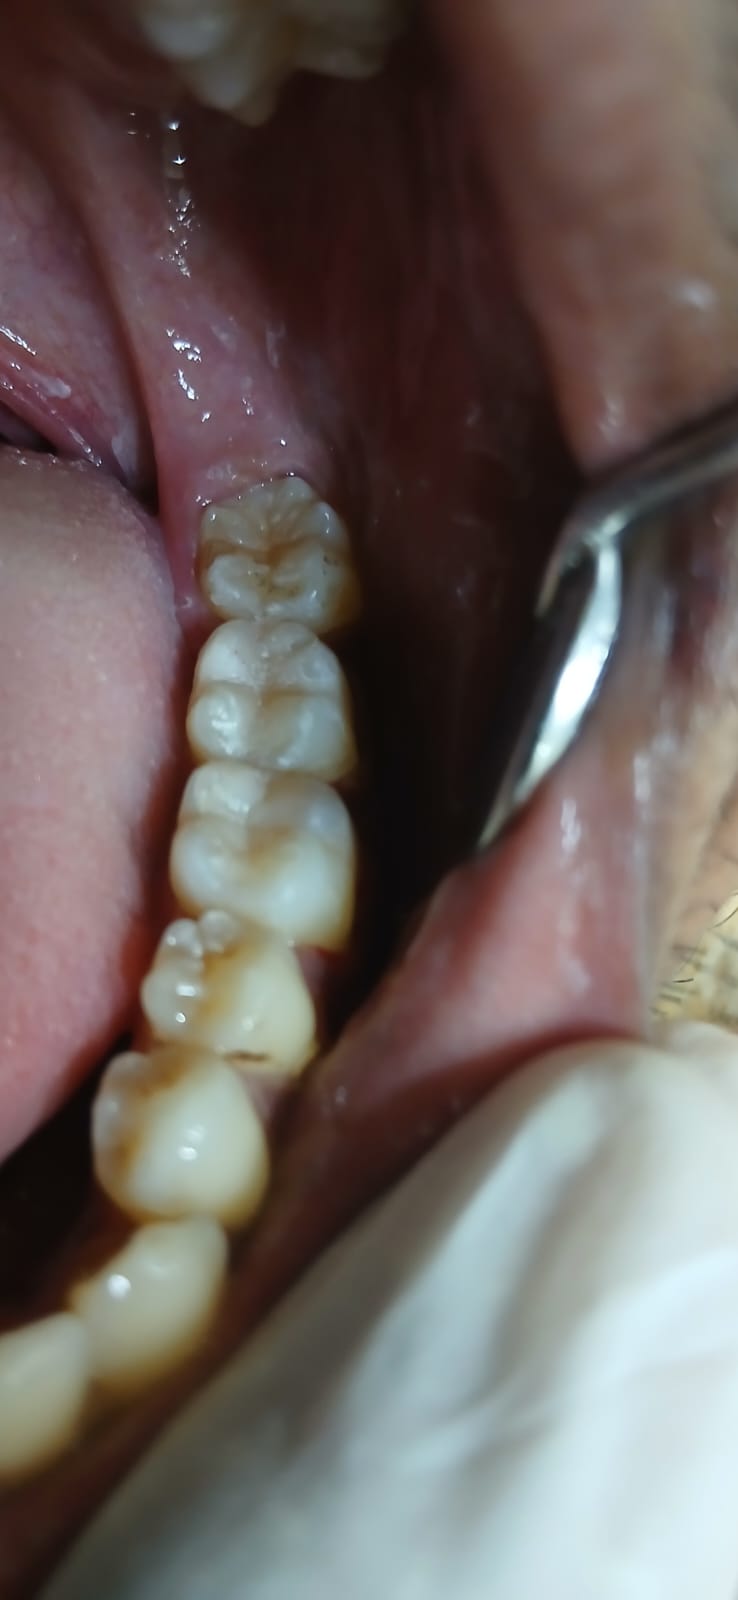

আগে ও পরে

আমাদের সফল কম্পোজিট রেস্টোরেশনের কিছু উদাহরণ

সামনের দাঁতের ক্ষয় মেরামত

ভাঙা দাঁত পুনর্গঠন

দাঁতের ফাঁক বন্ধ

ছবিতে ক্লিক করে বড় করে দেখুন। আরও কেস স্টাডি দেখতে ক্লিনিকে আসুন।